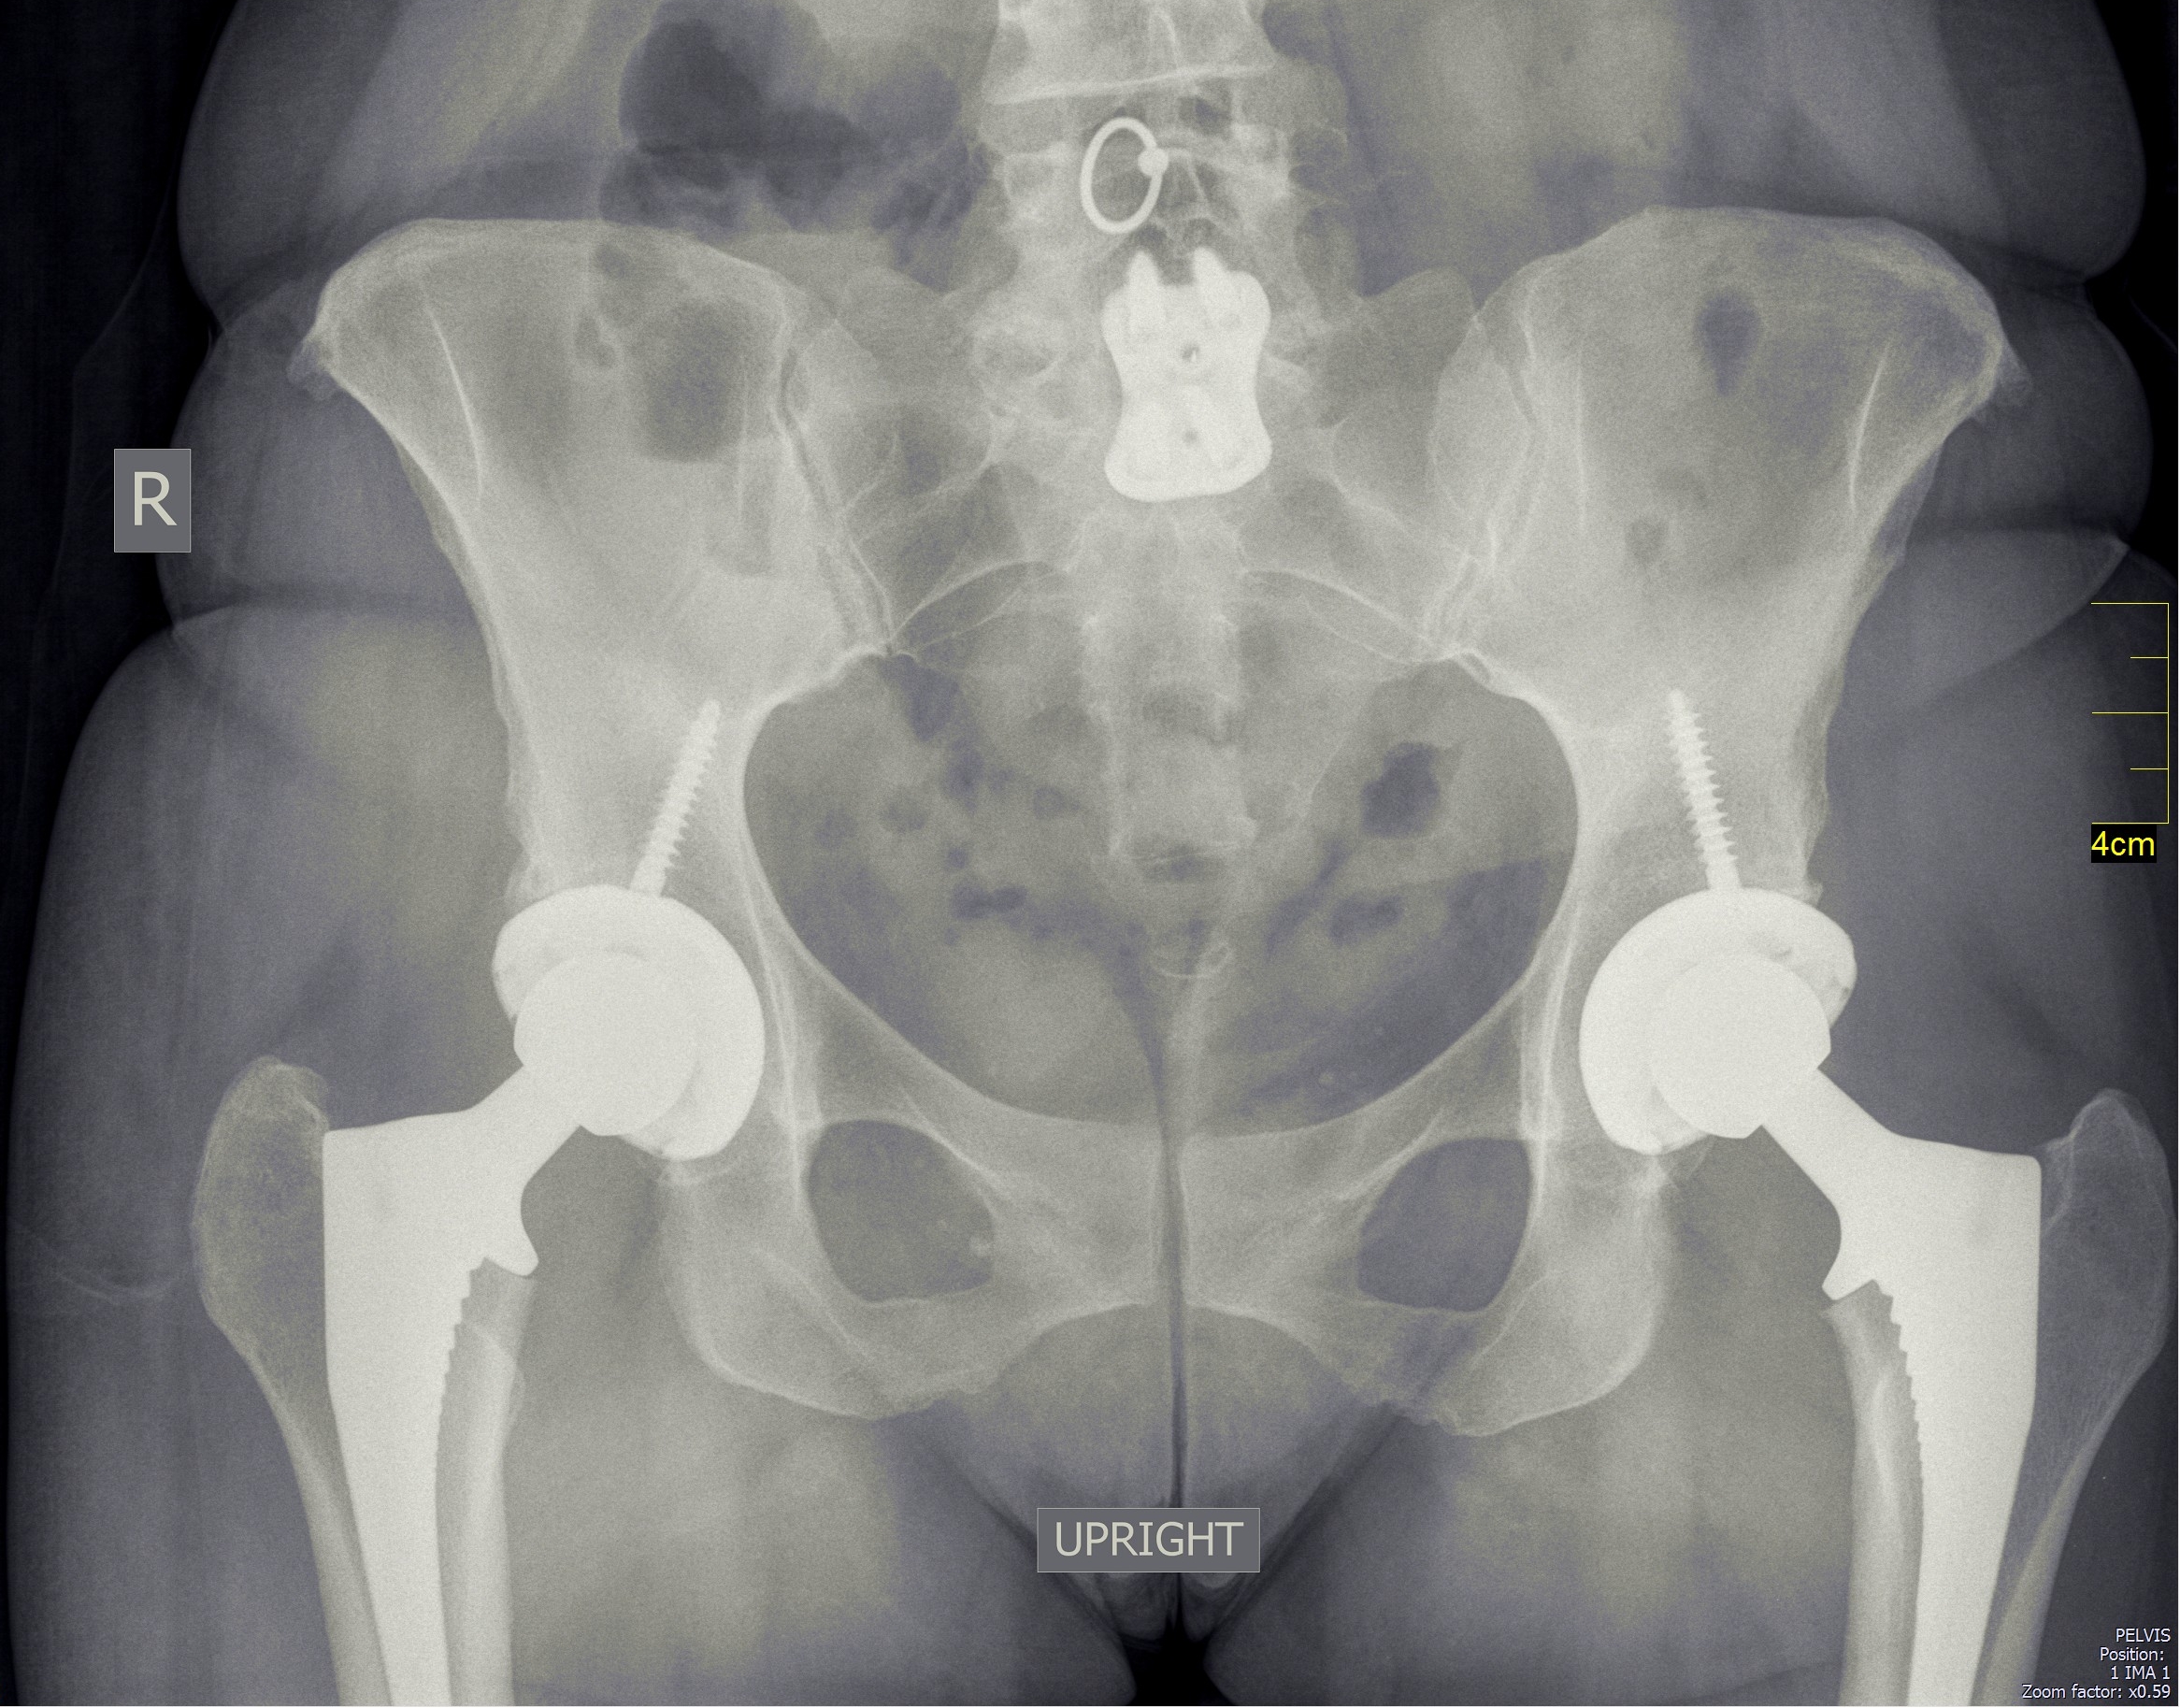

Since the patient is supine, it is possible to perform bilateral simultaneous hip replacements. Here's the appearance of my patient who had both hips replaced: